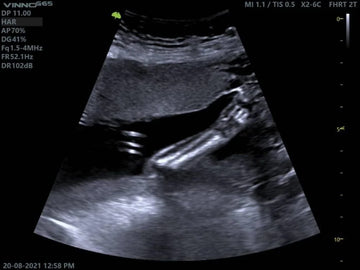

El ultrasonido de hígado y vías biliares es una técnica de imagen no invasiva que utiliza ondas de sonido para generar imágenes del hígado, la vesícula biliar y las vías biliares. Este procedimiento permite a los médicos observar en tiempo real el estado de estos órganos y detectar posibles anomalías, como inflamaciones, cálculos biliares o tumores.

El paciente se recuesta en una camilla mientras el médico coloca un gel sobre el área a examinar (generalmente el abdomen). Luego, se usa un transductor para emitir ondas de sonido que permiten crear imágenes en tiempo real.